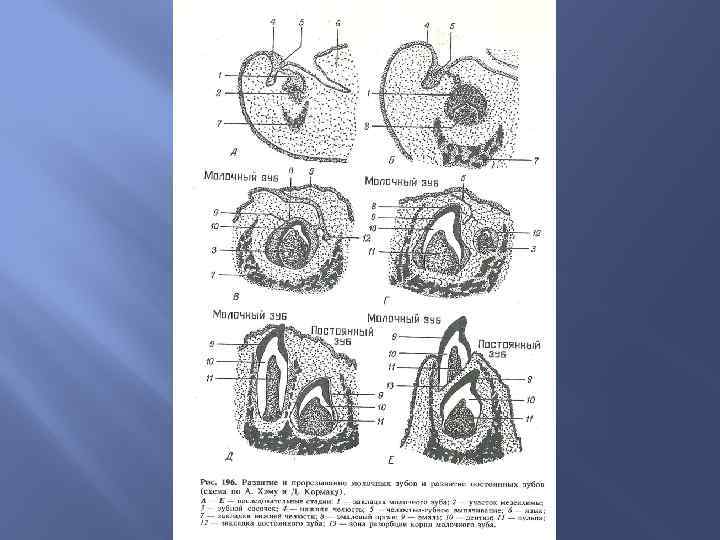

Развитие слюнных желез Околоушная слюнная железа развивается из эпителия ротовой полости, т. е. эктодермального происхождения. Подчелюстная и подъязычная слюнные железы развиваются из эпителия глотки, т. е. энтодермального происхождения. Развитие зубов На 7 -й неделе эмбрионального периода развития эктодерма верхних и нижних челюстных отростков образует зубные пластинки, погружающиеся в мезенхиму челюстных отростков. Из этих пластинок формируются эмалевые органы, клетки которых — адамантобласты образуют эмаль. Мезенхима образует зубной сосочек, адамантобласты которого образуют дентин, а ментобласты — цемент. ш

Развитие слюнных желез Околоушная слюнная железа развивается из эпителия ротовой полости, т. е. эктодермального происхождения. Подчелюстная и подъязычная слюнные железы развиваются из эпителия глотки, т. е. энтодермального происхождения. Развитие зубов На 7 -й неделе эмбрионального периода развития эктодерма верхних и нижних челюстных отростков образует зубные пластинки, погружающиеся в мезенхиму челюстных отростков. Из этих пластинок формируются эмалевые органы, клетки которых — адамантобласты образуют эмаль. Мезенхима образует зубной сосочек, адамантобласты которого образуют дентин, а ментобласты — цемент. ш

Аномалии развития зубов

Аномалии развития зубов